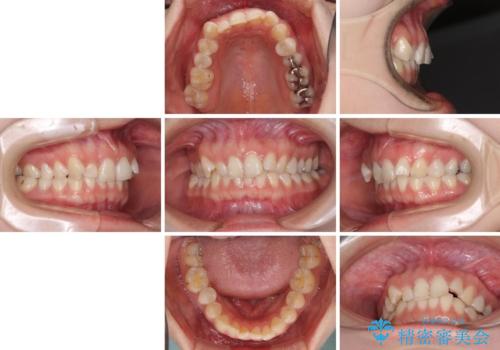

- 前歯の歯列不正を気にして来院された患者様です。

インビザラインでの矯正治療を希望されていましたが、奥歯の咬み合わせがインビザライン単独では改善困難と判断されたので、補助装置を併用することとしました。

まずは裏側の装置やワイヤー矯正を用いて歯列幅の狭い上顎を側方に拡大しつつ全体を後方に移動させ、その後インビザラインにて歯列を整えることとしました。

奥歯の咬み合わせの改善は、インビザライン単独では達成しきれないことがあるため、ワイヤー矯正などの補助装置を併用する場合があります。

インビザライン単独の場合と比べ、治療結果は大きく異なります。